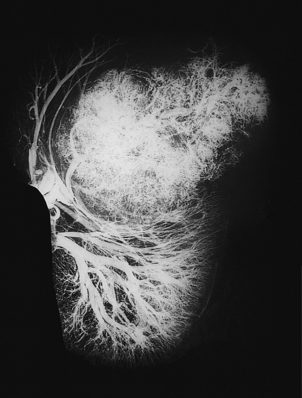

The stroma always contains blood vessels which perfuse the tumour (Fig. 11.4). The growth of a tumour is dependent upon its ability to induce blood vessels to perfuse it, for unless it becomes permeated by a vascular supply its growth will be limited by the ability of nutrients to diffuse into it, and the tumour cells will cease growing when the nodule has attained a diameter of no more than 1–2mm (Fig. 11.5). Angiogenesis in tumours is induced by factors such as vascular endothelial growth factor (VEGF). This action is opposed by factors such as angiostatin and endostatin which have potential in cancer therapy.

image

Fig. 11.4 Vascular stroma. Increased vascularity of a malignant tumour in a kidney, revealed by radiology after intra-arterial injection of X-ray contrast fluid.